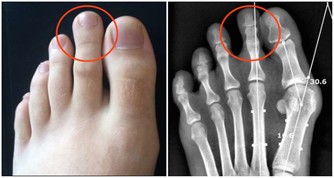

鞋底內側磨損較多

可能是兩腿的膝關節向外分離,導致小腿脛骨向內翻轉一定角度。嚴重的話會形成O形腿或「內八字」。如果邁著外八字腳步,說明腳趾向外的角度過大,時間久了,會讓膝蓋外移,雙腿變形。隨著年齡增長,可導致膝關節疼痛以及加速關節退化,甚至引起腰椎不適。

4、鞋底內側的磨損較多

鞋底內側的磨損較多,俗稱內八字,腳板過度內翻或是先天性的扁平足,膝關節向內側壓縮,易導致關節扭傷、損傷。

5、鞋底外側的磨損較多

鞋底外側的磨損較多,俗稱外八字,腳板過度外翻或是先天性的高弓足,膝關節向外側壓縮,嚴重時形成O型腿。

B.鞋跟內側都出現磨損

這種情況,是因為兩腿的膝關節向外分離、小腿脛骨向內翻轉了一定角度造成的。如果磨損十分嚴重,就意味著你的膝蓋已經外移,雙腿已經變形,變成「O形腿」或「內八字」。

隨著年齡增長,這種情況容易導致膝關節疼痛以及加速關節退化,甚至引起腰椎不適。